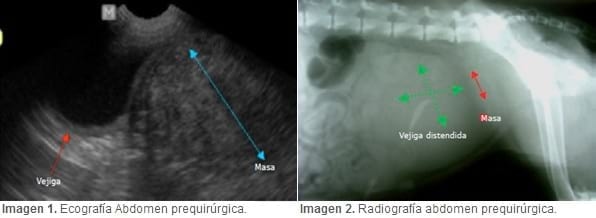

Se solicitó estudio ecográfico abdominal para evaluar las características de la masa palpable. Todos los exámenes imagenológicos se realizaron en la unidad de Diagnóstico por Imagen de la UST, sede Santiago. La ecografía abdominal informó sobre una masa, probablemente neoplásica en el útero, de 11,8 x 10 cm, con forma irregular, un parénquima heterogéneo y de ubicación dorsal al trígono vesical (Imagen 1). Además, la vejiga se apreció con moderada cantidad de orina y los riñones se encontraron disminuidos de tamaño, irregulares, con pérdida de la relación córtico-medular, signos indicativos de un proceso degenerativo crónico. Al estudio radiográfico de abdomen (imagen 2) se encontró una masa ubicada en la entrada de la pelvis, aproximadamente de 10 cm de diámetro, concordante con los hallazgos ecográficos. No se evidenciaron otras masas intrabdominales. A esto se sumó una marcada distensión vesical. El estudio radiográfico de tórax determino que se encontraba dentro de los parámetros radiográficos normales, sin evidencia de metástasis.